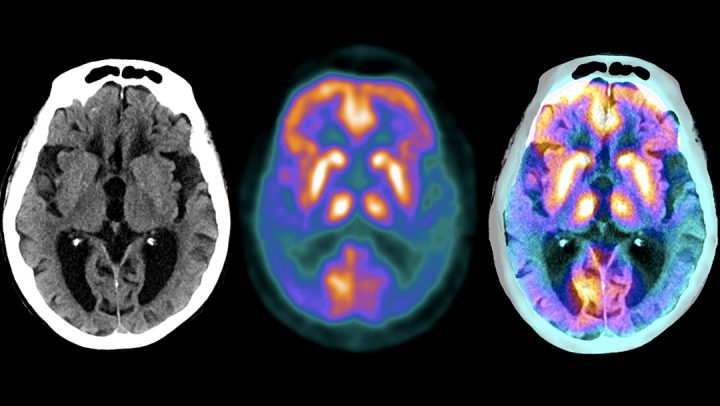

کاریگەری چەوری مێشک لەسەر دروستبوونی نەخۆشی ئەلزەهایمەر

دەیان ساڵە زانایان پێیان وایە هۆکاری سەرەکی توشبوون بە نەخۆشی ئەلزەهایمەر کۆبونەوەی پلاکی پڕۆتینی چەسپاوە لە مێشکدا. بەڵام ئێستا، توێژەران…

جەڵتەی مێشک چییە و هۆکار و نیشانەکانی چین؟

جەڵتەی مێشک حاڵەتێکی زۆر سەخت و کوشندەیە کە کاتێک ڕوودەدات کە ڕۆیشتنی خوێن بۆ بەشێکی مێشک تێکدەچێت. هۆکاری سەرەکی ئەم…